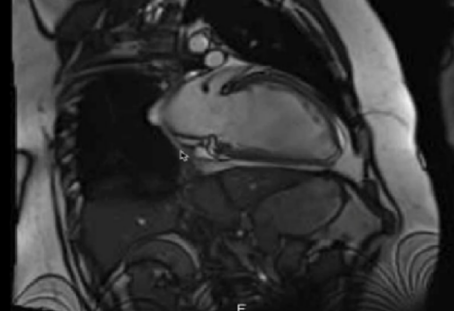

心脏MRI:EF 18%,左心室舒张末内径69mm,舒张末期左室容量298ml(正常52-195ml),收缩末期左室容量245ml(正常13-72ml),未见心肌纤维化或瘢痕的证据。

图3 心脏MRI